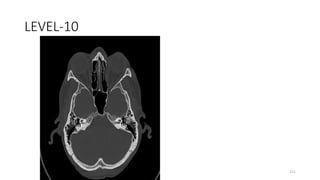

LEVEL-10

COCHLEA

INTERNAL AUDITORY CANAL

MIDDLE EAR WITH MALLEUS AND INCUS

SQUAMO OCCIPUT

Occipitomastoid suture

BODY SPHENOID

GREATER WING SPHENOID

Space connecting superior and inferior orbital

219

PETROUS TEMPORAL